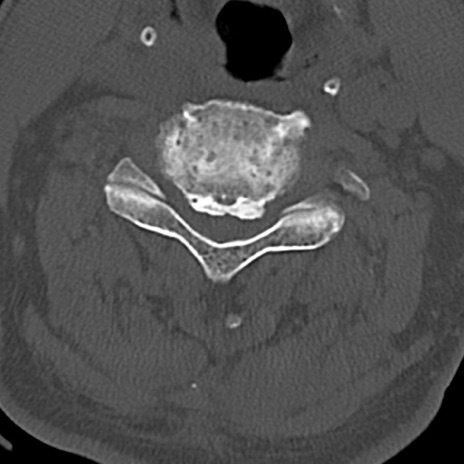

頚椎CT

横断像